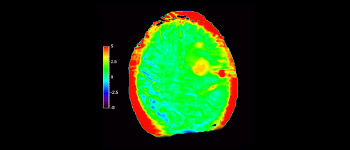

APTwイメージングでは、アミド基(NH)が対象となる。生体内のアミド基は、主にタンパク質やペプチドに含まれており、平均的には +3.5ppmの周波数に分布するとされる。アミド基のプロトンはバルク水から +3.5ppm離れた周波数帯に存在するため、交換プロトンの信号を抑制させる飽和パルスを +3.5ppmで選択的に照射する。飽和パルスによって信号が抑制されたアミド基のプロトンは、バルク水へ順次移動し、バルク水の信号を低下させる。飽和パルスの周波数を変化させながらバルク水の信号抑制を観察することで、間接的にアミド基を観察することができる(図1)。

CESTは、ごくわずかな共鳴周波数差(数100Hz)にあるプロトンを選択的に飽和させて画像化するため、静磁場B0(数十MHz)のわずかなズレでも、結果に大きな誤差が生じる。APTwイメージングでは、3D DIXON TSEシーケンスを用いB0補正を行っている。本シークエンスの利点は、3 point Dixonによる高精度のB0補正と撮像を一体化させB0不均一性に強い点と、スライスギャップなく3Dで広範囲の撮像が可能となった点である。これにより、B0不均一性に強く安定して広範囲のAPT強調像を撮像することができる⁴。